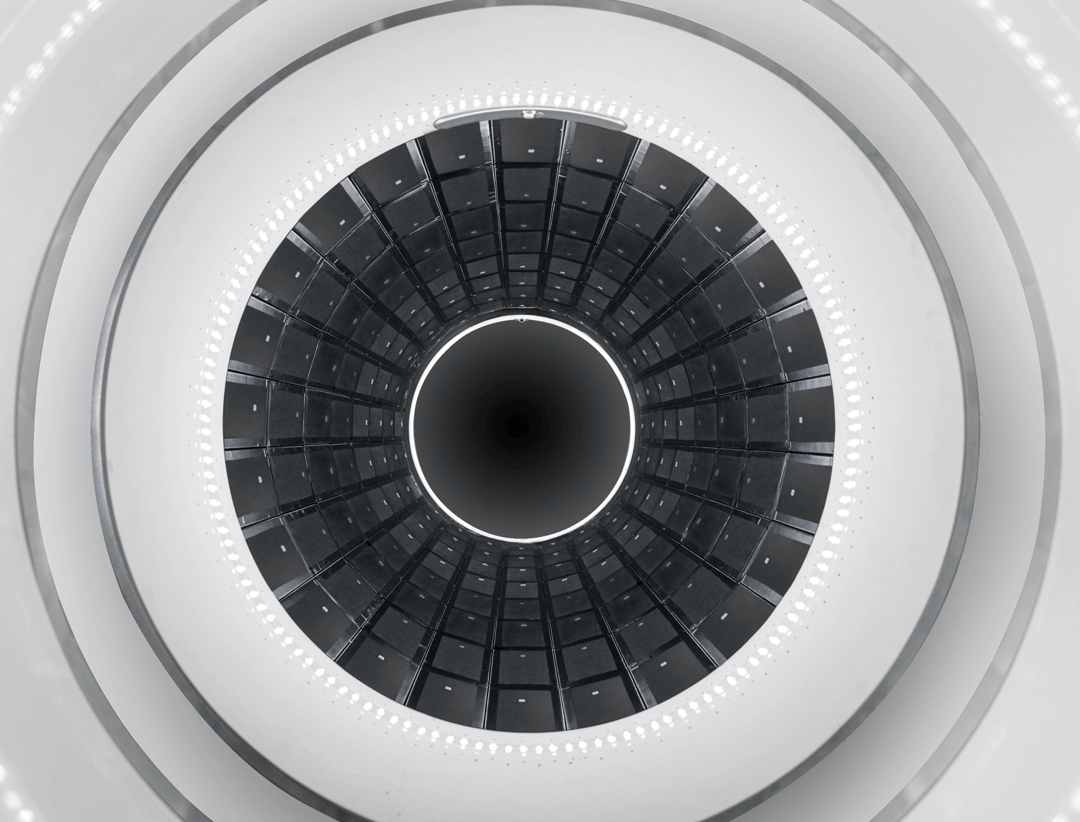

194 cm Axial FOV pentru acoperire total-body

uEXPLORER dispune de un câmp axial de vizualizare de 194 cm, cu 564.480 elemente cristaline, design modular și asamblare fără spații. Această arhitectură inovatoare oferă acoperire completă a corpului, reduce erorile sistemice și asigură imagini PET/CT cu rezoluție spațială ridicată și fuziune precisă.

PET Bore iluminat pentru o experiență relaxantă

uEXPLORER este dotat cu iluminare interioară a gantry-ului, creând un mediu mai prietenos și reducând anxietatea pacienților. Această funcționalitate sporește confortul și contribuie la o experiență PET/CT relaxantă și sigură.